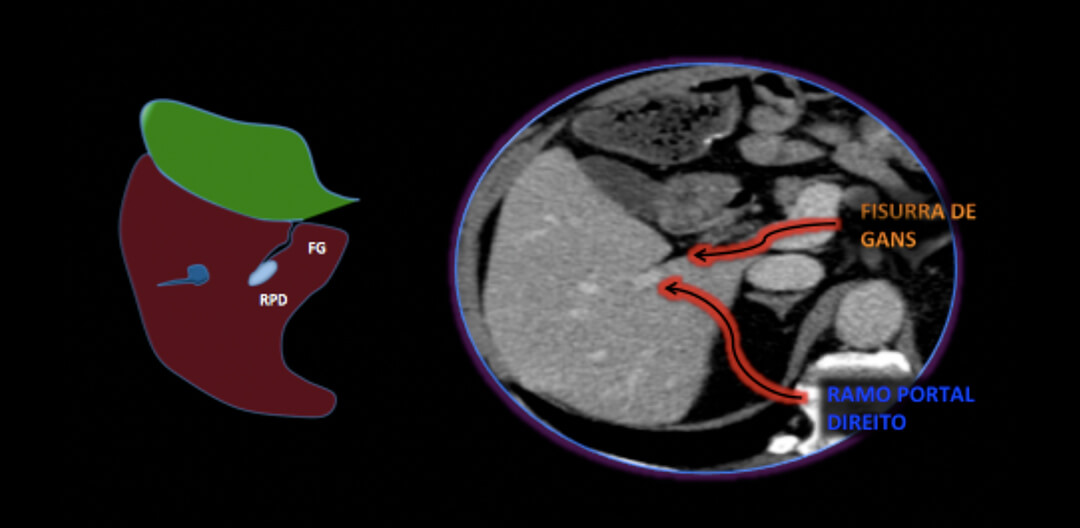

FISSURA DE GANS: Um reparo antômico esquecido pelo radiologista?